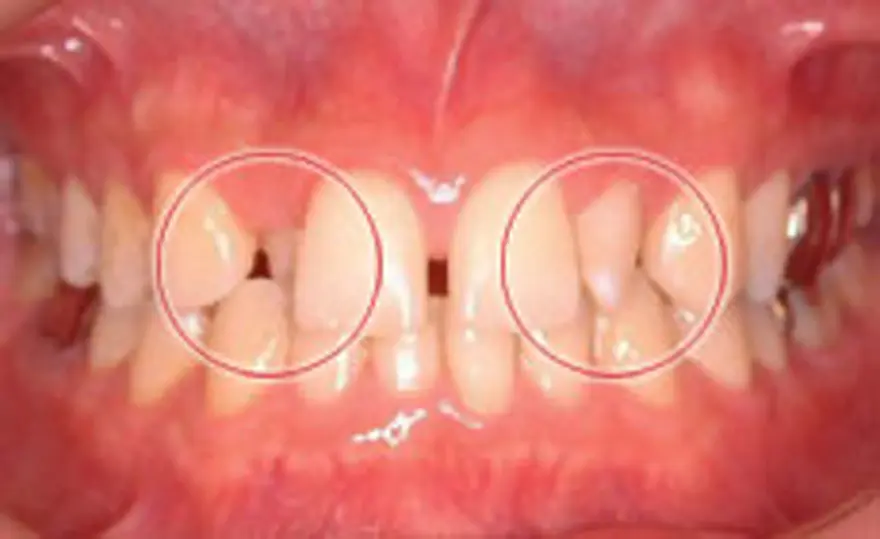

MTM(部分的な矯正)治療例3

正中離開のケース

| 患者さまの年齢・性別 | 30代・男性 |

|---|---|

| 治療期間 | 5ヵ月 |

| 治療費(税込) | 187,000円 |

| 主訴 | 前歯の隙間が気になる。 |

| 診断名・主な症状 | 正中離開 |

| 治療に用いた主な装置 | セルフライゲーションブラケット装置(デイモンシステム) |

| 治療内容 | 中央があいている原因の1つとして考えられる上唇小帯を切除しています。こういったケースでは再度隙間があいてくることも多いため、保定装置の長期の使用や歯の裏側からの固定が必要となります。 |

| 抜歯部位 | 非抜歯 |

| 通院回数・メンテナンス頻度 | 5回 |